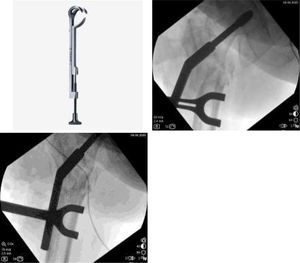

The plate to use should be a DHS (dynamic hip screw, several trademarks sell it), with at least 6 holes, and an angulation of 135–150°.

Over-valguization of the nonunionIn this moment, the DHS (of at least 6 holes) is introduced to the previously introduced cephalic screw. To correct the position of the femoral head, the plate should be placed just over the diaphyseal bone. To accomplish this, a Lowman retractor is recommended. Softly, the retractor is tightened, and the plate comes to the diaphyseal bone, reducing the nonunion (Fig. 6).

Only one dynamic system has been used in this indication.5 A dynamic sliding hip screw (DHS) of 135–150°. That is the technique presented in this paper. The nonunion zone is opened, the varus deformity overcorrected, and then fixed in a completely dynamic fashion, allowing the patients to bear weight from the first operative day. Even a few patients have been reported,4 results seem promising, with 100% healing and nearly no complications.